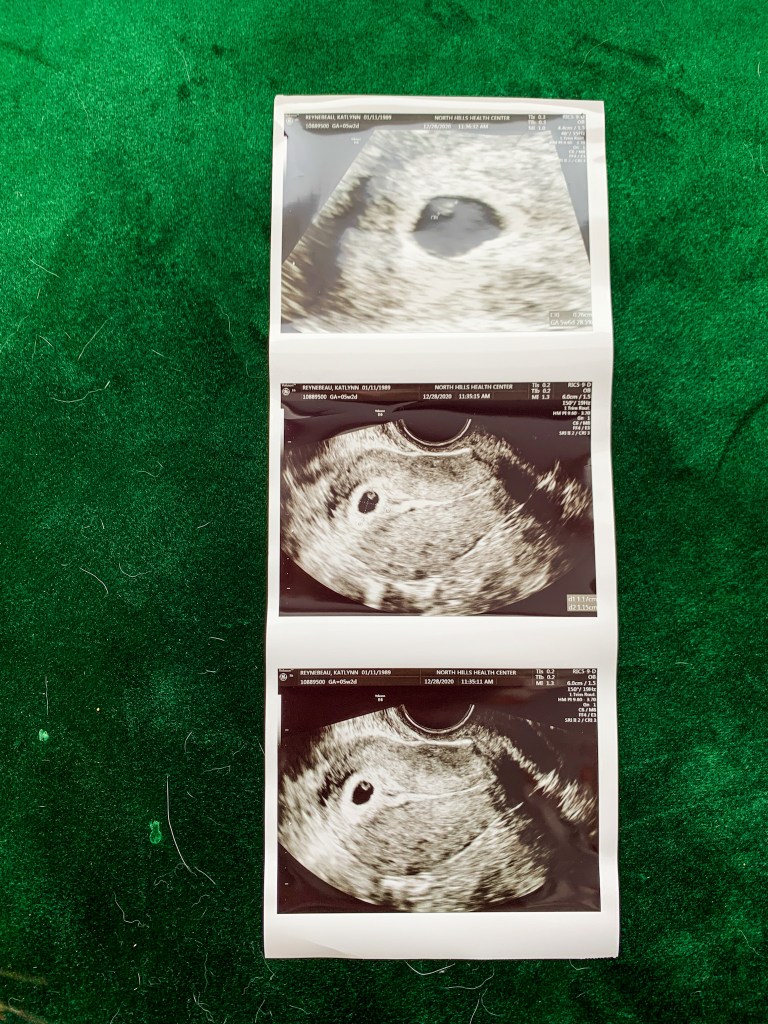

December 2020: Found out we were pregnant, my grandpa passed away, and I began spotting

January 2021: Confirmed heartbeat on my birthday 1/11, confirmed no longer a heartbeat on 1/20, scheduled a D&C on 1/22, found out after surgery my brother had died.

But before moving onto our current pregnancy, I would be remiss if I did not take the day to celebrate the sweet life we never knew. The day we found out we were officially pregnant (December 28th, 2020) we started imagining our life with you in it. Having 2 under 2, how August would be a big brother, telling our families and even long term plans like summer birthday parties. So happy due date to our second pregnancy.